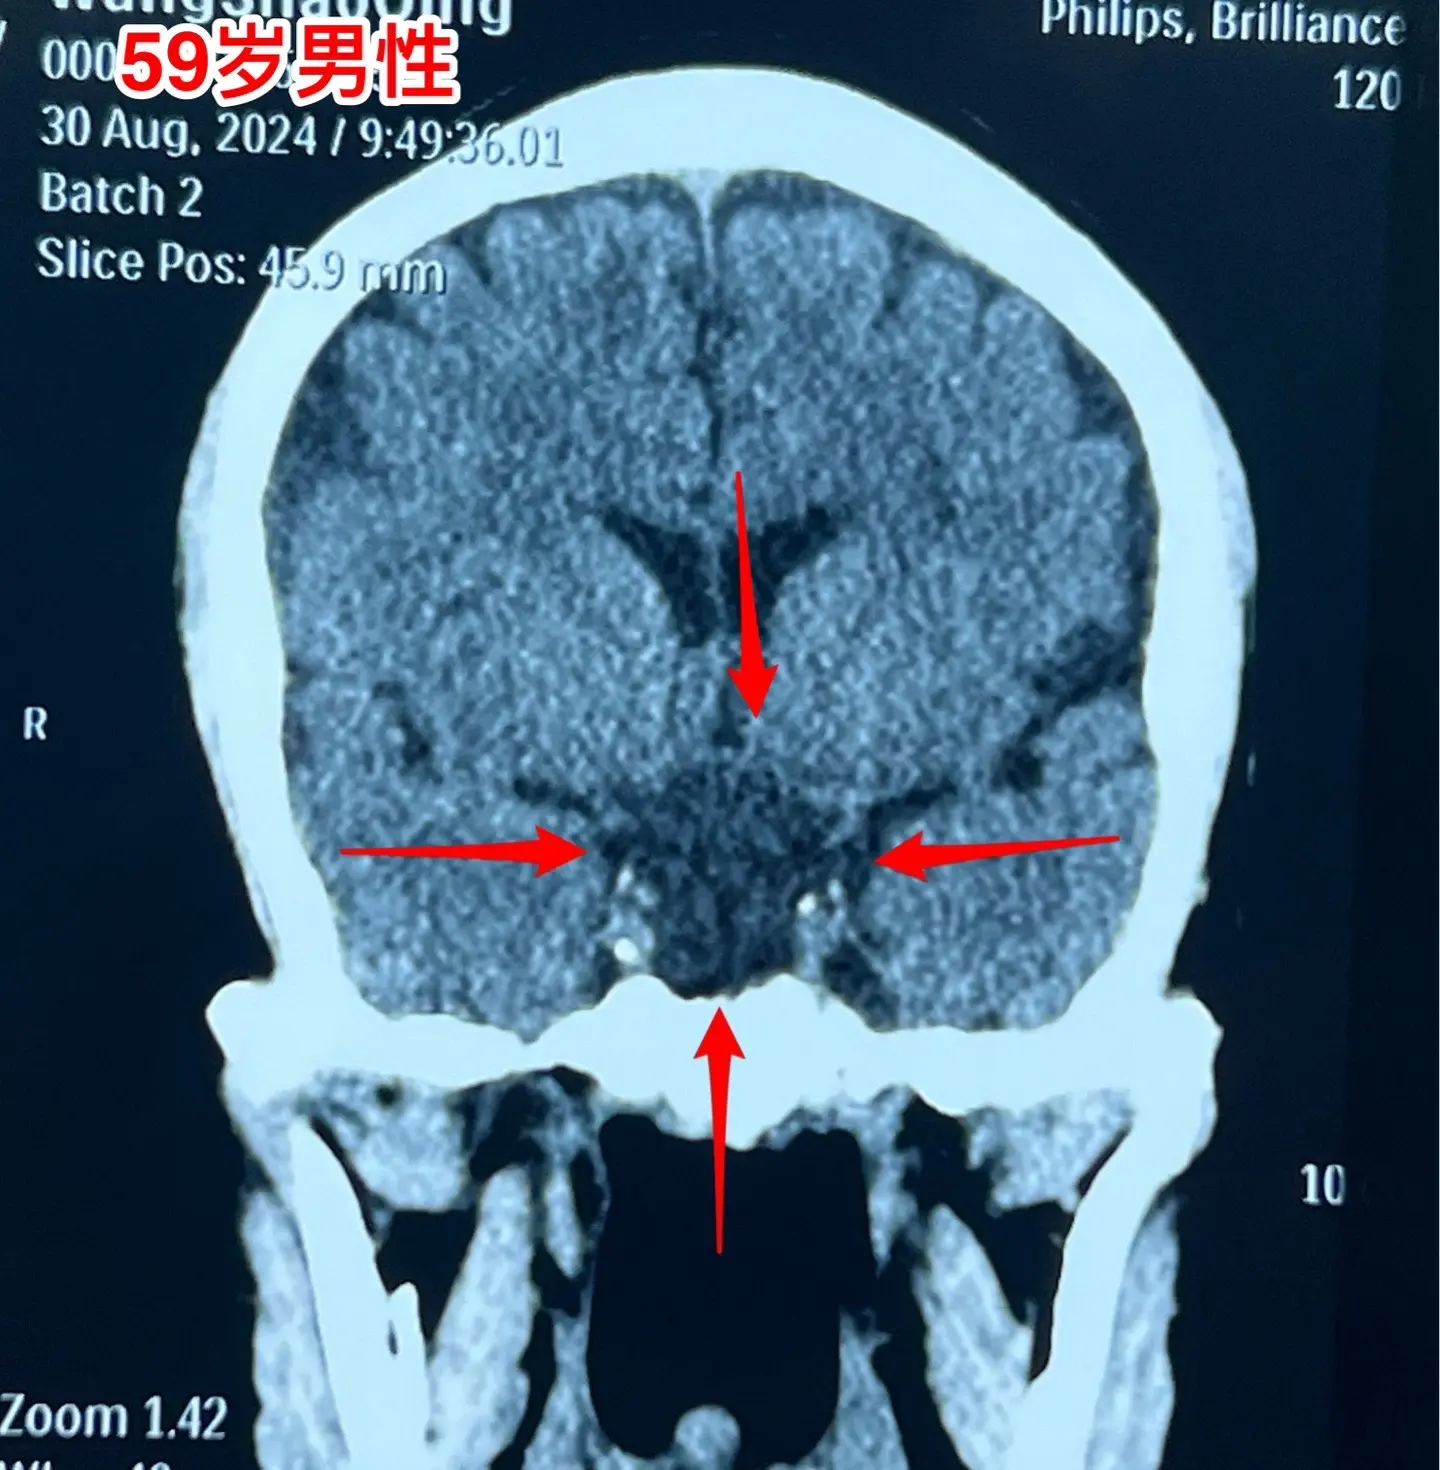

头痛、视力下降、多饮多尿、体重下降。59岁洛阳市男性,近三年感头痛,近一年半感觉视力下降,以为是老花眼,未就医。近9个月多饮多尿,夜间睡眠很差,白天精神很差。近半年体重下降25斤。 2024.8.23到医院就诊,作头部磁共振发现颅咽管瘤。2024.9.5在我科行开颅手术切除颅咽管瘤。手术中发现肿瘤是囊性的,内壁有瘤结节,没有钙化,所以是乳头型颅咽管瘤,肿瘤得到完全切除。手术后双眼视力显著改善。(今年的第133例颅咽管瘤)